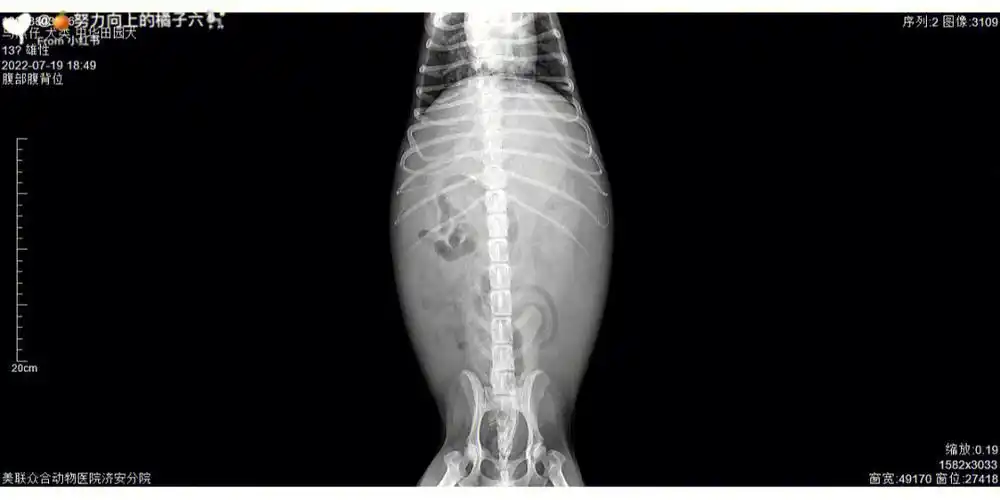

更新一下吧,家里的狗狗已经走了,但是还是希望能帮助到大家,而且还有